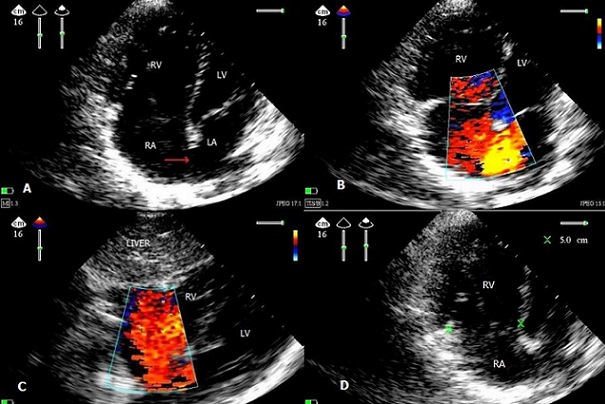

Atrial septal defect (ASD) is characterized by a defect in the interatrial septum allowing pulmonary venous return from the left atrium to pass directly to the right atrium. ASD account for 10% of all congenital heart disease, and as much as 30 % of congenital heart disease presenting in adulthood. There are four types of ASD that can be recognized as the seat of the port: ostium secundum, the most common, they are located in the area of the oval fossa, and are usually well focused, to differentiate from a patent foramen ovale as in our patient , isolated secundum atrial septal defects account for approximately 7% of congenital cardiac defects ; sinus venosus, high location, near to the anastomosis of the pulmonary veins ; ostium primum , low, can be integrated into a more complete atrioventricular canal ; coronary sinus, a very rare form, this type is a fenestration or a total absence of the roof of the coronary sinus, into the left atrium. In general, elective closure is advised for all ASD with evidence of right ventricular overload or with a clinically significant shunt (pulmonary flow [Qp] to systemic flow [Qs] ratio >1.5). Closure of an ASD is not recommended in patients with a clinically insignificant shunt (Qp-Qs ratio 0.7 or below) and in those who have severe pulmonary arterial hypertension or irreversible pulmonary vascular occlusive disease who have a reversed shunt : right to left with hypoxemia. We report the case of a men aged 35 years, admitted to the ICU for a left pneumo-hemothorax with rib fracture resulting from an accident of the highway, drained emergency. Auscultation of the heart sounds: a systolic ejection murmur, respiratory variations in the splitting of the second heart sound; in the ECG: presence of incomplete right bundle branch block with atrial flutter. The echocardiography at the bedside with multiple effects showed dilatation of the right ventricle, and confirming the atrial septal defect type ostium secundum with left-right shunt noting that the subcostal window is a better impact on the diagnostic to ask for two reasons: ultrasound are perpendicular, Doppler is strictly aligned . Hypertension of pulmonary artery measured at 45 mmHg. The patient is referred to the cardiovascular consultation after its release for therapeutic cardiology discussion.